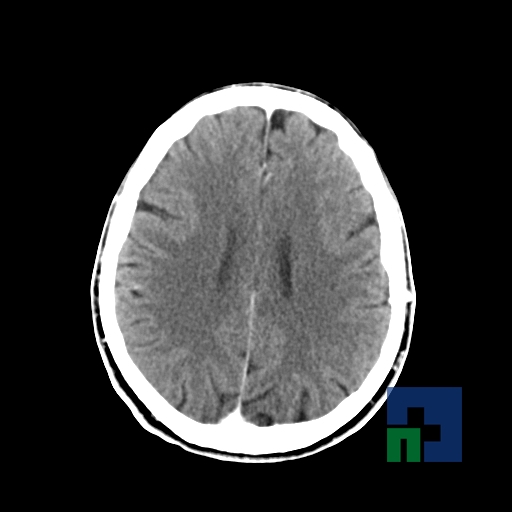

Examinare de rutină cerebrală, nativ și cu substanță de contrast (SDC) pentru diagnosticul:

- Accidentelor vasculare cerebrale ischemice sau hemoragice

- Tumorilor cerebrale

În cazul traumatismelor cranio-cerebrale:

- Evaluarea deplasării liniei mediane

- Evaluarea cisternelor perimezencefalice

- Diagnosticul edemului cerebral, a contuziei cerebrale, a leziunilor axonale difuze edematoase/hemoragice, a dilacerării cerebrale, a hematomului intraparenchimatos posttraumatic, a hematoamelor subdurale/extradurale (acute, subacute, cronice), a hemoragiei intraventriculare, a hemoragiei subarahnoidiene

- Diagnosticul traumatismelor de bază de craniu

- Diagnosticul fistulei LCR

- Diagnosticul herniilor cerebrale

- Diagnosticul fracturilor:

- Tumorilor cerebrale:

- Empiemul subdural

- Abcesul cerebral

- Fistula carotido-cavernoasa

- Higroma

- Atrofia cerebrală regională